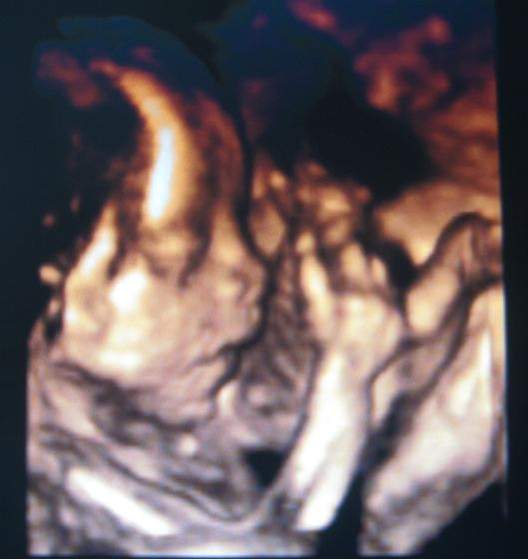

Przedstawiam Wam mojego pięknego wciąż Aleksandra

płeć potwierdzona, Olek pokazał jajuszka... Co do szczegółów wizyty napiszę na wątku głównym...